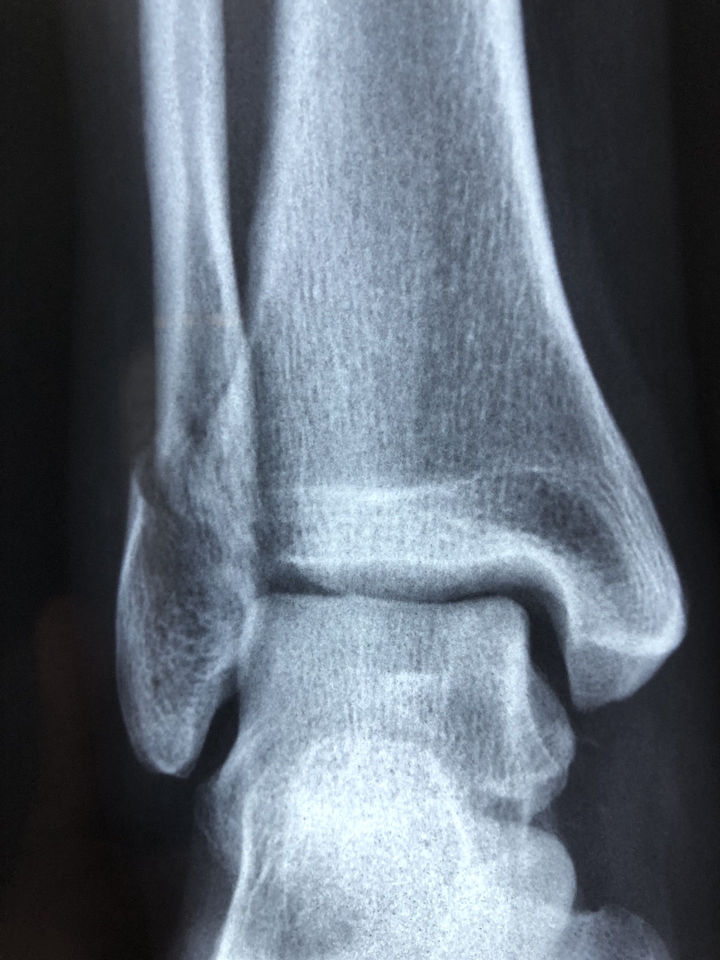

Ankle fracture

A fracture is a partial or complete break in a bone. Fractures in the ankle can range from the less serious avulsion injuries (small pieces of bone that have been pulled off) to severe shattering-type breaks of the tibia, fibula or both.

Ankle arthritis

Ankle arthritis is a clinical condition in which the joint that connects the foot to the leg, known as the tibiotalar or ankle joint, has damaged or worn out cartilage.